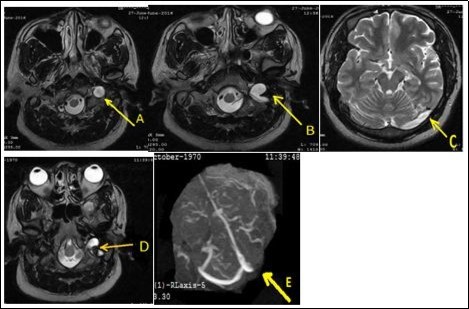

A 46-year-old man was admitted in neurology on June 27, 2016 for left occipito-temporal headache progressively for 2 weeks associated sometimes with nausea and rarely vomiting. He underwent a physical examination of an ophthalmologist and then by a physician of Otorhinolaryngology who had not diagnosed any pathology. On admission, somatic examination was normal. Routine biologic test were normal kidney, hepatic, ionogram, blood count were normal, sedimentation rate was 22 mm /h and C-reactive protein was less normal). The activated cephalin time and the plasmatic homocysteinemia were normal. The activity of protein S and the activated protein C were normal. The chest X-ray and electrocardiogram were normal. The brain ct-scan suspected a left transverse sinus thrombosis. Venous magnetic resonance angiography displayed a left internal jugular vein thrombosis extended to the left transverse sinus associated with a left ethmoidal sinusitis (Figure 1). The cervical doppler was normal. Treatment with low molecular weight heparin was initiated and then replaced with antivitamins K to achieve an international normalized ratio (INR) between 2 and 3 in addition to ofloxacin for 2 weeks and paracetamol. After three months, its remains a partiel jugular thrombosis with persistance of complete transverse sinus thrombosis.

Figure 1.Thrombosis of the left internal jugular vein extended to the transverse sinus (A, B, C). After three months of anticoagulant therapy, it remains a partial thrombosis of the jugular vein (D) and complete thrombosis of the transverse sinus (E).

Thrombosis of the left internal jugular vein extended to the transverse sinus (A, B, C). After three months of anticoagulant therapy, it remains a partial thrombosis of the jugular vein (D) and complete thrombosis of the transverse sinus (E).